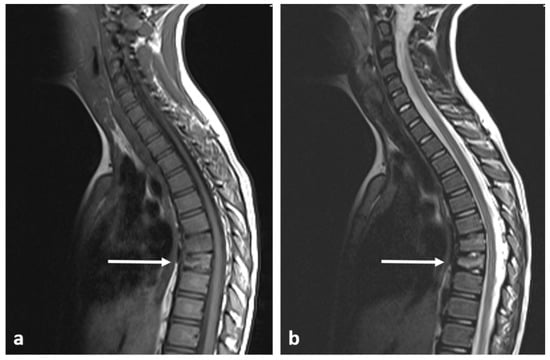

3.3. Osteoblastoma

| Osteoblastoma | Expansile lucent lesion. Sclerotic rim. Bone destruction. Variable intralesional ossification. | Low to intermediate T1 signal and intermediate to high T2 signal. Surrounding soft tissue oedema, extra osseous soft tissue component. |